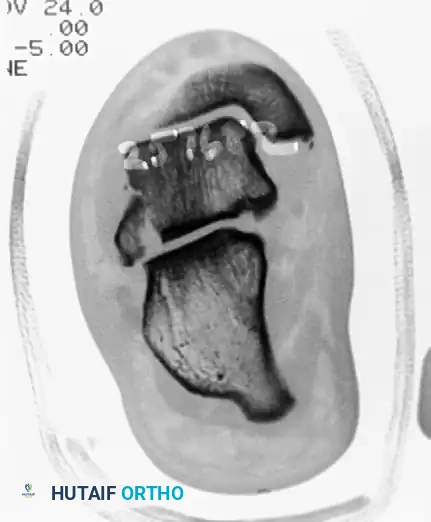

Preoperative lateral radiograph demonstrating a suspicious osseous density posterior to the talus, often difficult to distinguish from an os trigonum without advanced imaging.

Preoperative sagittal CT scan clearly delineating a large, displaced posterior process fracture with intra-articular extension into the subtalar joint.

Postoperative lateral radiograph following successful excision of the posterior process fragment. The patient subsequently became asymptomatic with full restoration of FHL excursion.